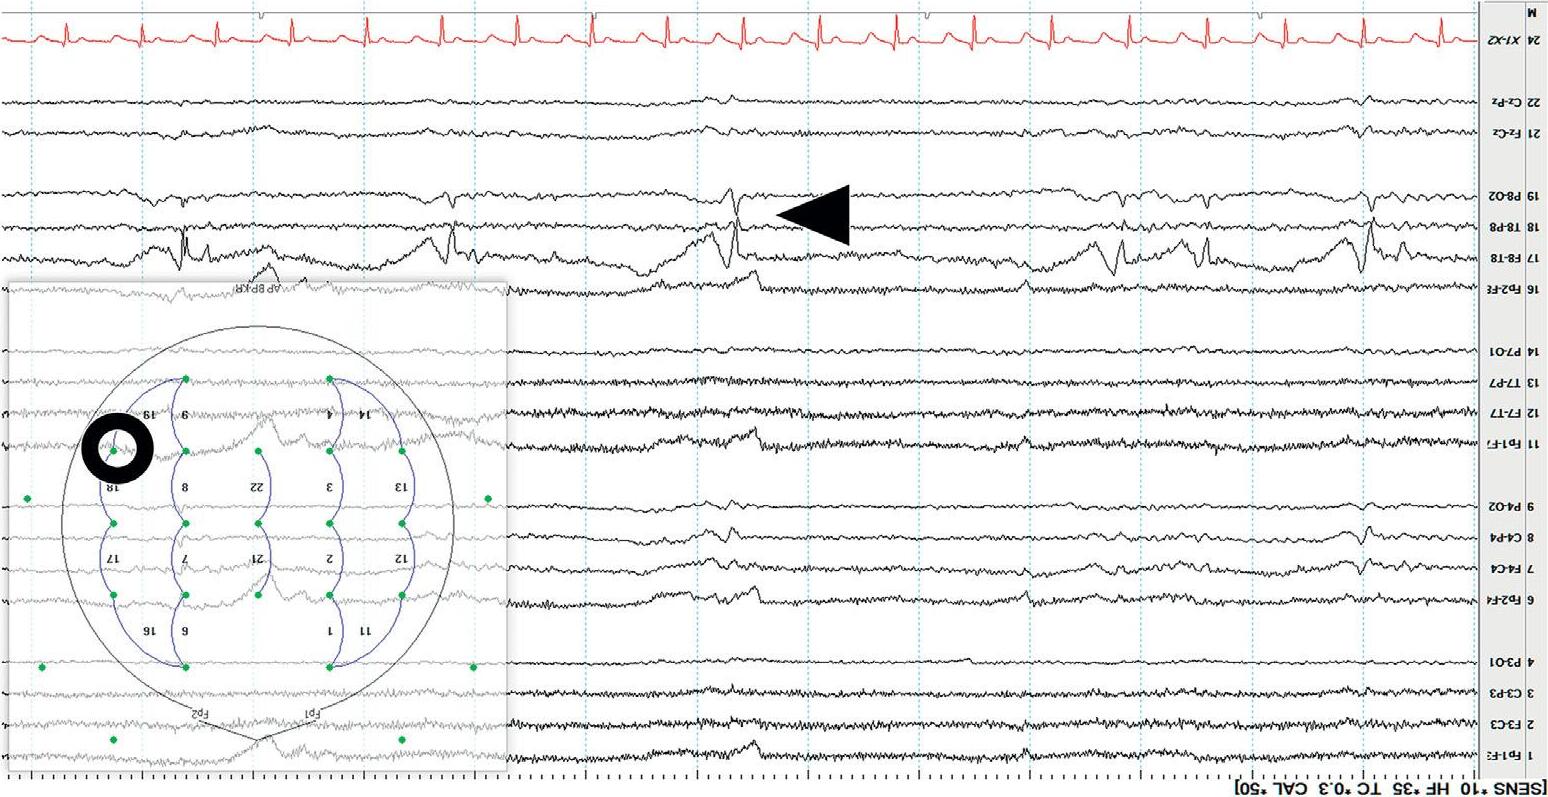

Display(Parameters) Atypicalbedsidedisplayusingalongitudinalbipolarmontageisshownin Figure1.3(a). Variationstothisformatexist.Commonly,theleftandtheright temporalchainsarestackedtogetherfollowedbytheleftandrightparasagittal chains.Thismakesiteasytocomparethetemporalandparasagittalregionsof bothhemispheresforasymmetry.Readersshouldknowthatthetemporal regionsarealsothemostepileptogenicsofocusingonthesechannelsyields results!Thetopbarofarecordingshowsthesensitivity,filtersettings,and timebase.

Mostdisplaysshow10or15secondsperpageofEEG. Figure1.5 showsa typicaldisplayusingthelongitudinalbipolarmontagewithexcessivemuscle artifactbefore(a)andafter(b)applicationof30Hzhighfrequencyfilter.

Figure1.5(a) EEGwithHFFsetto70Hz.

Figure1.5(b) ThesameEEGwithHFFsetto30Hz.